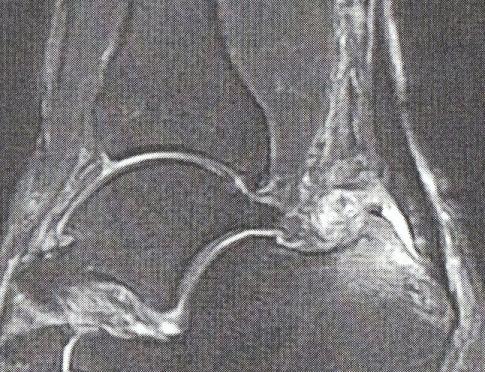

〇今月初めから右足の踵が痛く、歩く時にも右足に体重をかけられませんでした。〇2週間前に病院でレントゲンを撮ってもらいましたが、踵にたくさん骨棘があり、それが原因かも知れないとの診断でした。〇昨日MRIを撮ってもらったところ、アキレス腱の付け根に炎症があり、アキレス腱滑液包炎との診断でした。(MRIの右側が踵後方でアキレス腱の付け根が白くなっている部分が炎症です。)〇病院のトレーナによると、大きすぎるシューズを履いた影響と左足の安定が悪く、右足の踵・指の可動範囲が狭く、右足に負担がかかっているのではとのことです。〇これから以下のリハビリとケアを毎日することとなりました。1.アイシング 10分2.タオルを足指でたぐる 2回3.右足の踵をストレッチチューブ押さえて20往復 2回4.左足の股関節のストレッチ 30秒5.股関節のストレッチ 30秒〇意外と左脚の強化が主なのです。〇明日からリハビリ終わるまで、各項目の実施状況をレポートします。